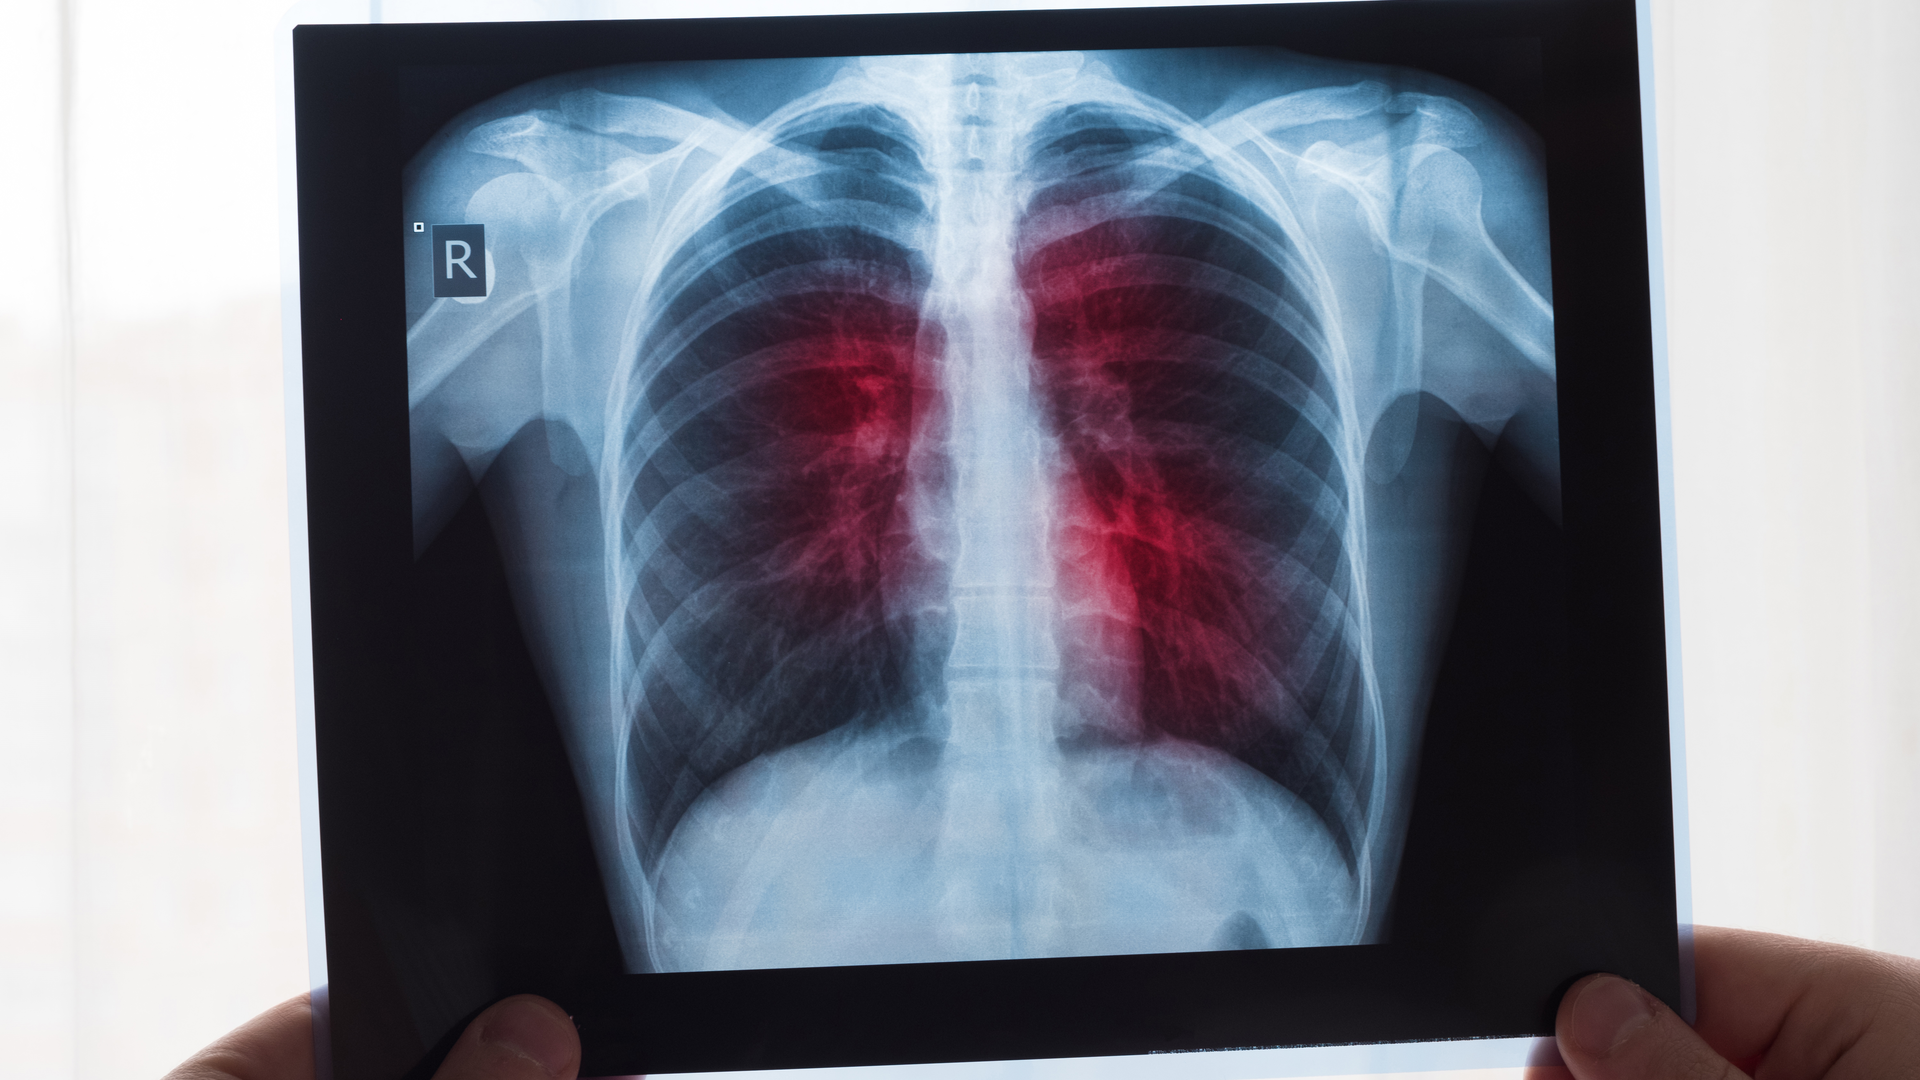

One way to mitigate such problems is to accurately predict the prognosis of patients who test positive for COVID-19. Doctors generally use chest X-ray radiography (CXR) images to assess the condition of patients. By analyzing signs of pneumonia in these images, they can infer if the patient is likely to need admission to the ICU soon. In turn, this can help with optimal allocation of hospital resources. Unfortunately, this process is labor intensive, time consuming, and suffers from variability in diagnoses, which is a major issue especially during large outbreaks.

But what if artificial intelligence (AI) gave us a helping hand? In a recent study published in the Journal of Medical Imaging, a team of researchers from the Department of Radiology of the University of Chicago has developed a deep learning-based model that can predict if a patient will need intensive care by analyzing their CXR images.